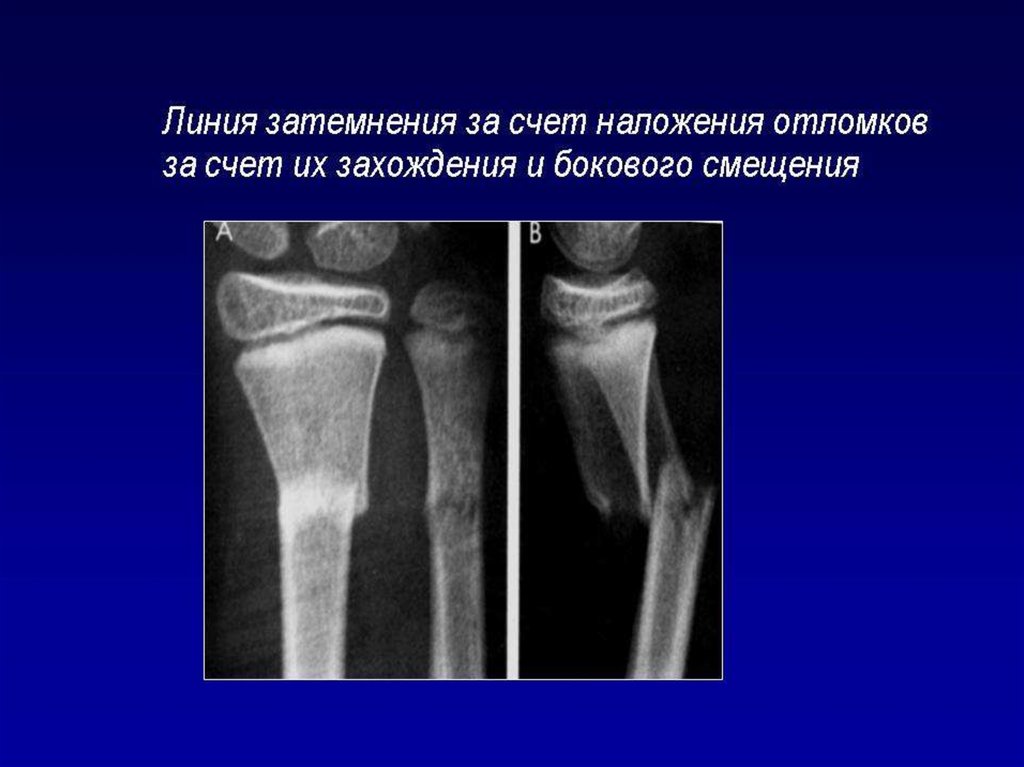

Лучевое исследование костно-суставной системы. Методы исследования. Семиотика